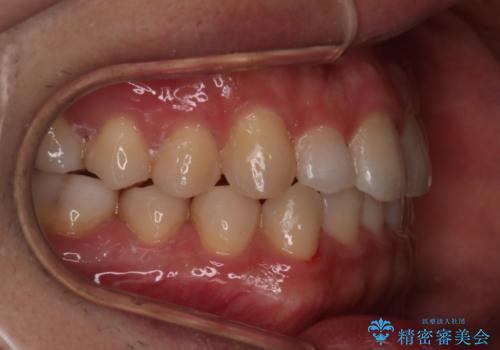

- 前歯のがたつきを主訴に来院されました。初診時、右上2番の口蓋側転位と右下7番の舌側傾斜が認められました。

インビザラインにてIPRと歯列弓拡大を行い、ゴム掛けで噛み合わせを改善する治療計画を立てました。

マウスピースの使用時間が短いため、シュミレーション通り進むか不安でしたが

治療期間1年で、主訴である前歯のがたつきを改善出来、

奥歯の噛み合わせも良くなりました。